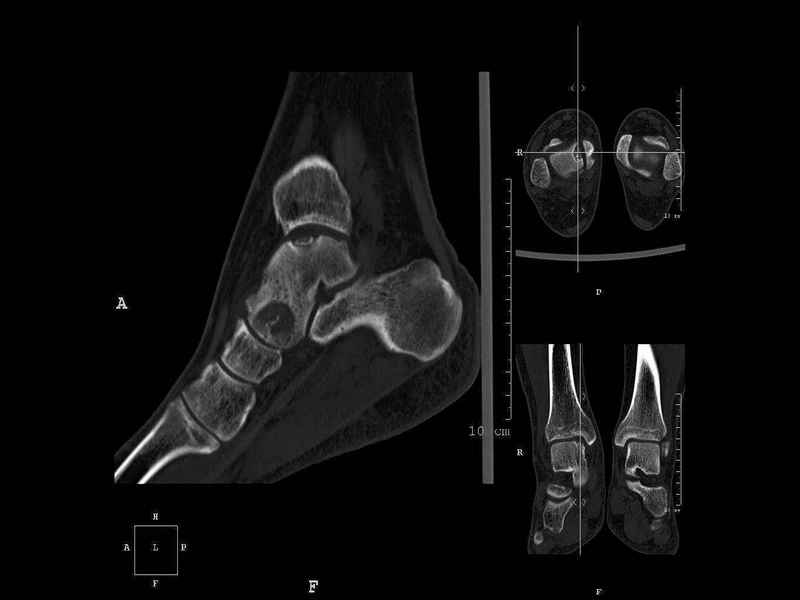

Уважаемые коллеги, обратился за помощью пациент, мужчина, 25 лет. С жалобами на болевой синдром в области голеностопного сустава и среднем отделе стопы. Травму отрицает. Со слов, болевой синдром в течении 1 года. Последние 1-1.5 мес периодически вынужден пользоваться костылями. После ограничения нагрузки боли уменьшаются.Соматически здоров. До появления болей активно занимался рукопашным боем. На СКТ картина рассекающего остеохондрита блока таранной кости, киста шейки таранной кости с признаками импрессии суставной поверхности. А также - разрастания переднего края б\берцовой кости сопровождающиеся клиникой импиджмент синдрома. Предполагаемый план лечения- удаление свободного фрагмента суставного хряща из трансмаллеолярного доступа с рассверливанием поверхности дефекта, кюретаж кисты шейки с заполнением полости биокомпозитом + дебридмент переднего отдела голеностопного сустава. Прошу высказать своё мнение, за и против, предполагаемого плана лечения. А также по возможности ответить на вопросы: 1. Есть ли необходимость в улучшении васкуляризации таранной кости (например подтаранный артродез). 2. Учитывая планируемое применение биокомпозитного цемента целесообразно ли заполнение им дефекта блока таранной кости с моделированием края суставной поверхности.

СТ чётко демонстрирует секвестр, но открыв сустав вероятно, что хрящ тарана окажется интактным и только пальпацией/ ЭОП можно будет

идентифицировать локализацию секвестра. Если вы с этим столкнетесь, то секвестрэктомию я бы предложил сделать не со стороны суставной поверхности тарана, а со стороны угла тарана, субхондрально кюрретаж стенок, разнонаправленную туннелизацию спицей или 1.1мм сверлом и заполнить дефект спонгиозным графтом.